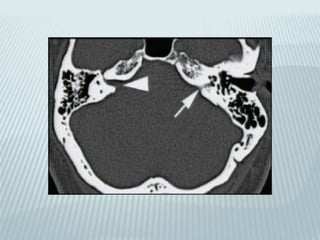

Middle ear

effusion

Cholesteatoma